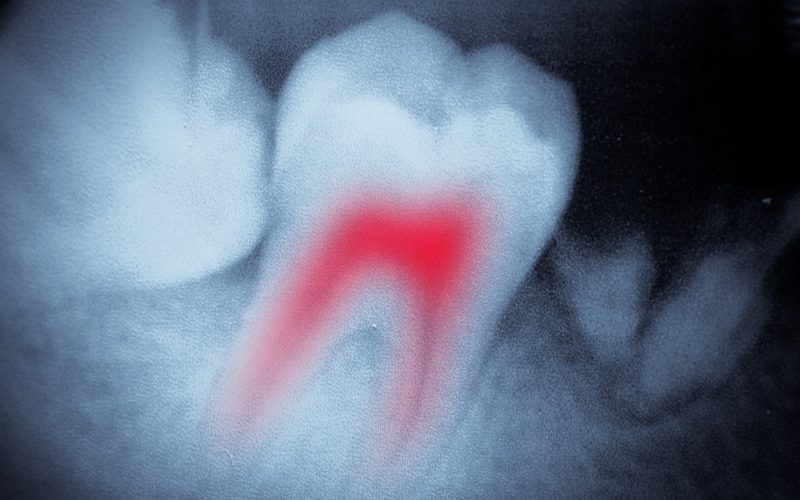

A crack in the tooth produced either by mishap, gum disease, or by a cavity, can lead germs directly to the inside of the tooth. When in contact with germs, dental pulp – essential to the health of your teeth – can decay quickly. A root canal allows you to keep your tooth rather than having it extracted.

We perform precise, pain-free, cost effective root canals for patients experiencing pain from extensive decay, tooth trauma, or gum disease.

The following may indicated decaying dental pulp: